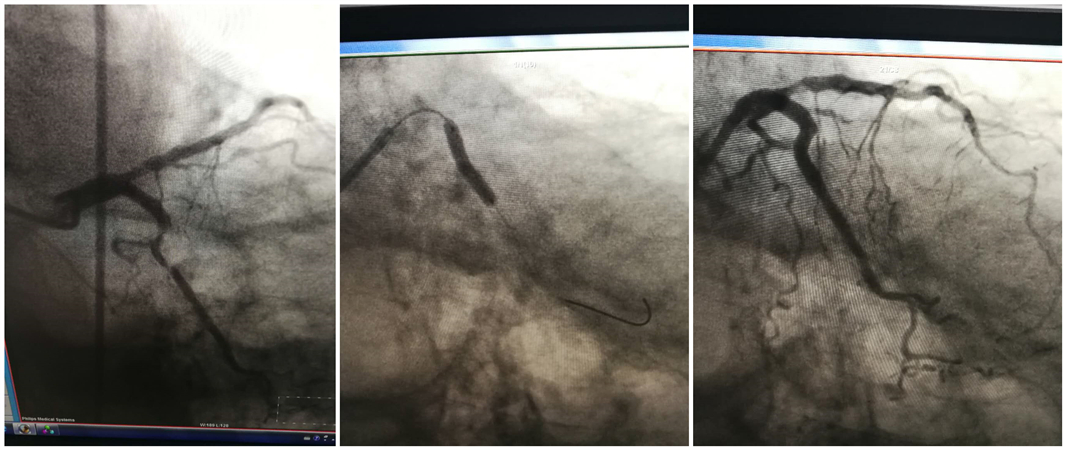

患者慕某,男性,72岁,冠心病心肌梗死支架植入术后5年,此次主因一过性晕厥一个月入我院心内一科治疗,经神内三科会诊,进行头颈部CTA检查提示右侧颈椎动脉闭塞、右侧锁骨下动脉重度狭窄,对颅内供血造成严重影响。为尽快解决患者病痛,在心内一科宝云龙主任、神内三科杨卫东主任的支持与指导下,两个科室联合会诊、认真讨论,决定于4月10日晚由神内三科徐鹏医生主刀为患者进行右侧锁骨下动脉支架植入术,随后由心内一科郑崔成医生施行冠状动脉造影确定患者心脏血管具体情况。两位主刀医生周密计划,详尽准备,手术顺利进行。不出所料,术中发现患者冠状动脉回旋支同样重度狭窄,随时有发生心梗的可能,郑崔成医生在与患者家属充分沟通后,随即进行冠脉支架植入术,开通濒临闭塞的血管。术后患者头晕、胸闷等症状消失,恢复良好,用患者家属的话说:“整个人都精神了”,家属对我院心内一科与神内三科团队一再表示感谢。

神内三科徐鹏医生表示在以往这类疾病的诊治过程中,患者需要在心内科及神内科两个科室分别做造影进行诊断及相应的介入治疗,至少经历2次手术、反复住院或转科,不仅会加重患者的痛苦,而且还将增加手术费用,延长住院时间。而同时期进行冠脉支架和颈部血管支架置入术,可减少患者重复手术的风险及痛苦,可同步解决脑血管病和心脏问题,真正做到心、脑血管疾病同治同康复!

心内一科郑崔成医生也说道:“动脉粥样硬化是心脑血管病共同的病理基础,是一个全身性疾病,只是由于累及部位不同、发病先后不一,才出现不同的临床症状。对这类患者其中一种疾病进行手术时,另一个经常成为术后严重并发症的导火索。因此在治疗上,‘心脑联合’才是最佳方案。”